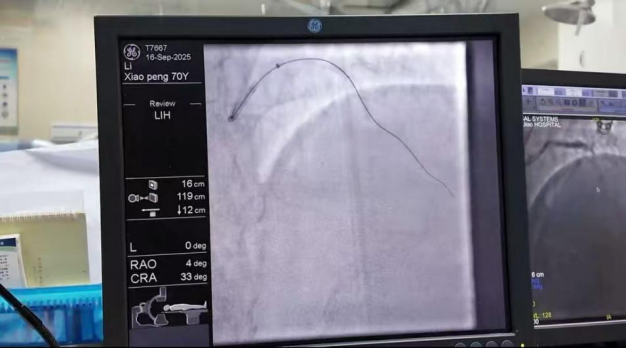

患者为70岁男性,病史长达4年,反复出现胸闷、憋喘等症状,曾被诊断为“急性心肌梗死、急性心力衰竭”,冠状动脉造影显示其左主干+三支病变,血管全程钙化,患者辗转求诊于北京、济南等多家国内知名医疗机构,曾尝试开通血管不成功,后因血管条件差、手术风险极高,均建议药物保守治疗。近一年来,患者心力衰竭病情急剧恶化,需每2-3个月住院一次,药物效果日益减退。2天前患者症状再次加重,考虑血管堵塞加重导致缺血性心肌病进展,复查冠脉造影后显示冠状动脉弥漫性全程钙化,左主干狭窄90%、右冠脉完全闭塞、前降支完全闭塞,回旋支狭窄50%,造影结束后介入医生直呼该患者仍能存活“真是奇迹”。

9月16日下午,该手术在济南南郊医院介入诊疗科顺利完成。齐鲁医院ECMO(体外膜肺氧合)团队关键时刻提供技术支持,为患者生命体征稳定筑牢防线;心内科石少虎主任、党争程主任团队凭借丰富经验,成功开通血管,并处理左主干钙化狭窄;麻醉科刘凯团队全程守护,确保手术麻醉安全;介入室、手术室曲亚云团队高效配合,保障手术流程顺畅;重症监护室余恒平团队提前做好准备,为术后患者监护衔接到位。